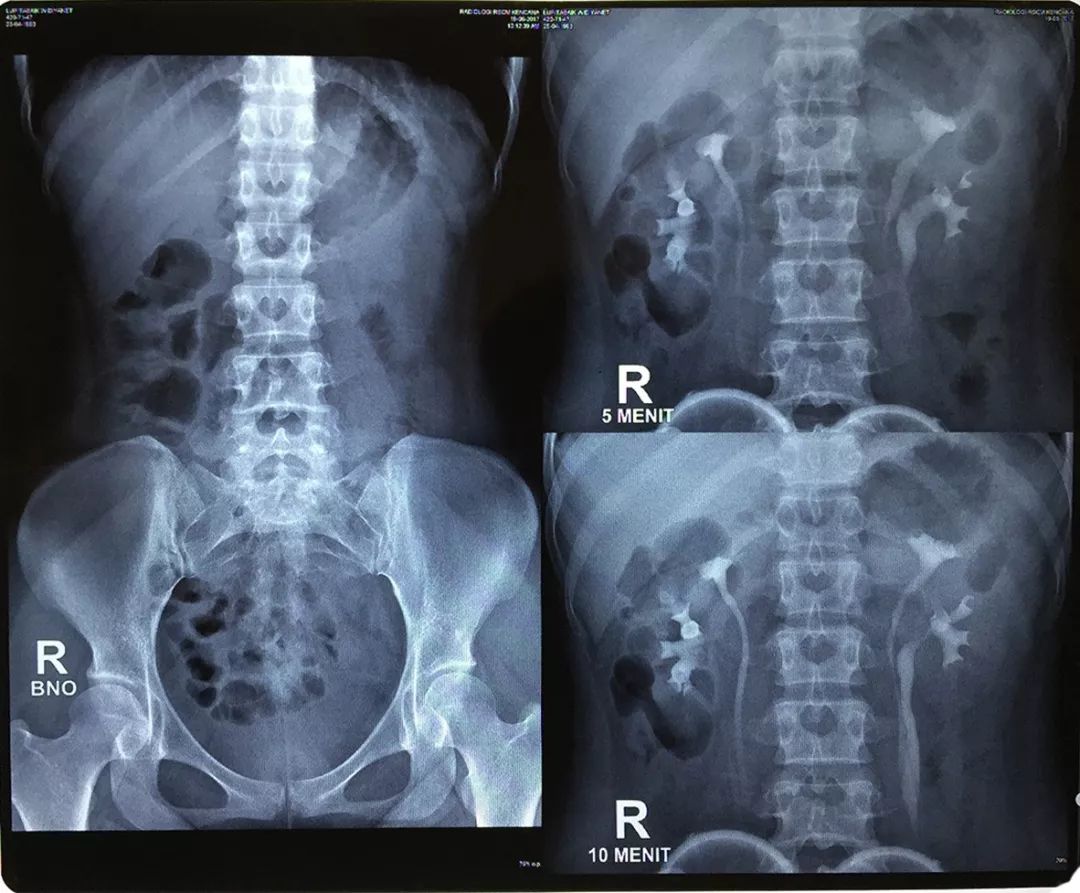

肾移植受者女,38岁,患有ESRD,经历高血压失控后准备接受活体肾移植,肾源来自她25岁的妹妹。术前静脉肾盂造影显示,供者双肾重复输尿管和重复肾盏系统。双侧重复输尿管分别在右侧小盆腔水平和左侧第五腰椎椎体水平融合(图1)。由于腹腔镜手术可行性较好,取左肾作为供肾。

图1 静脉肾盂造影显示供者双肾重复输尿管和重复肾盏系统。两侧肾脏都有双重集合系统和重复输尿管。右输尿管在远端融合为一体,左输尿管在中端融合为一体。(点击可放大)